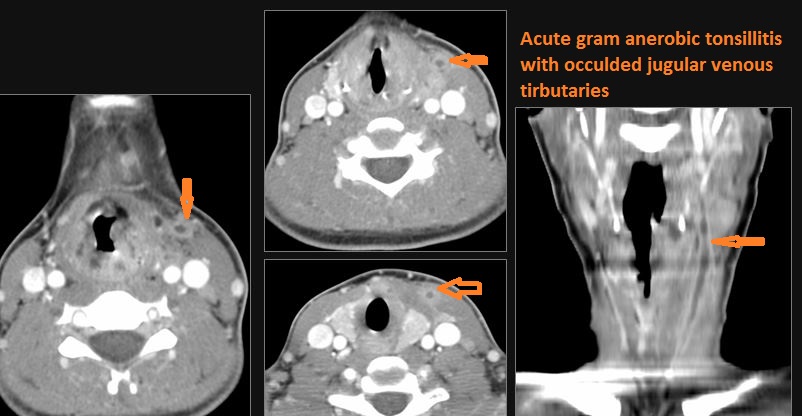

There is excessive enhancement or thickening of the mucosa or hypertrophy of the palatine or lingual tonsillar tissue or the lymphoid tissue along the glossotonsillar sulci and posterior pharyngeal wall.

There is abscess at the periphery of the lymphoid tissue of the palatine tonsil within the potential peritonsillar space.

Cervical Lymph Nodes

If there is suppurative cervical adenopathy the purulent material outside the lymph node(s) capsule(s).

Vascular Findings